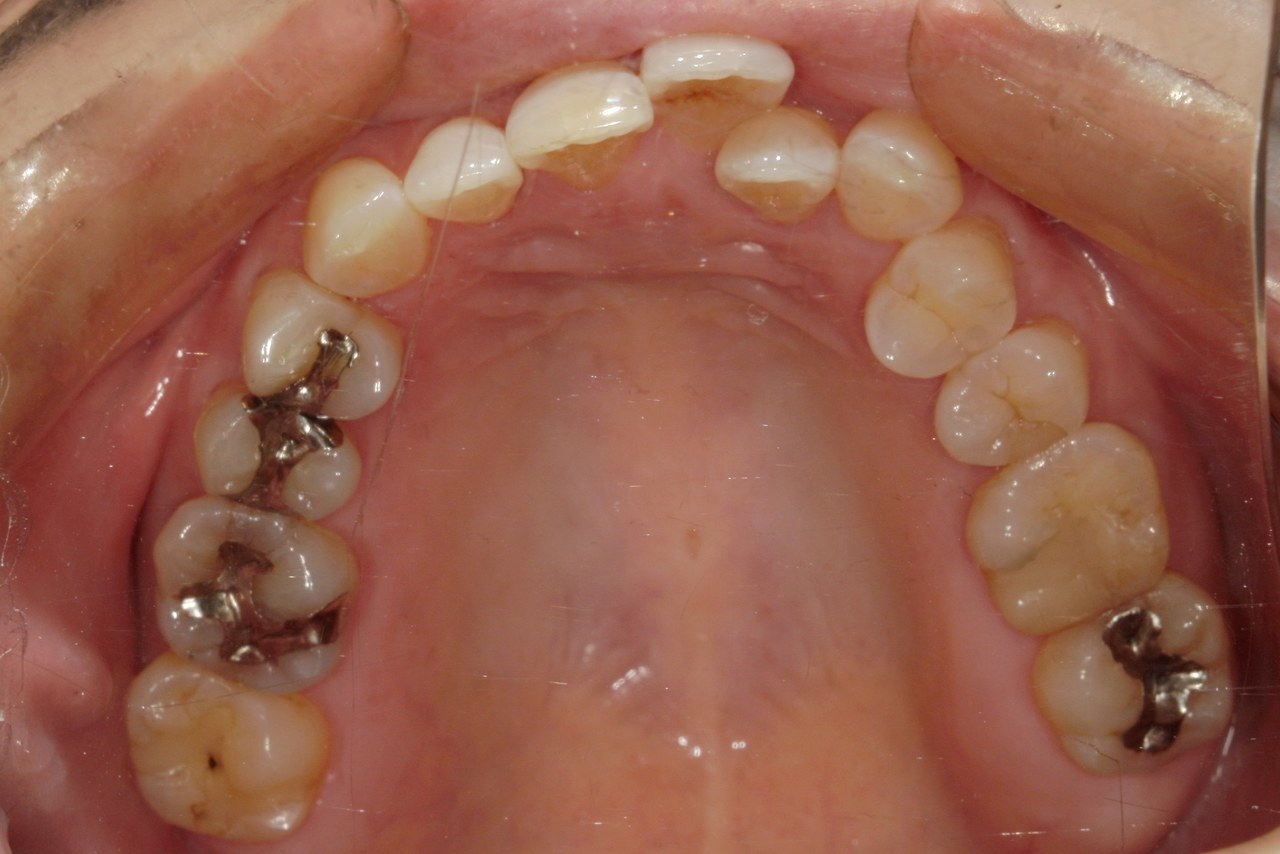

Before

浜松市中央区・自動車学校前駅のインビザラインの症例

K.M 20代女性

上の前歯が前方に出ていて横顔が気になるとの主訴でご来院。上下犬歯から犬歯までの6本が噛み合うよう、全体的に歯を内側に移動させることで、前歯の噛み合わせを整え叢生と開咬を治療しました。

​治療の期間:R5. 7/5〜R7. 1/17

​治療の価格:66万円